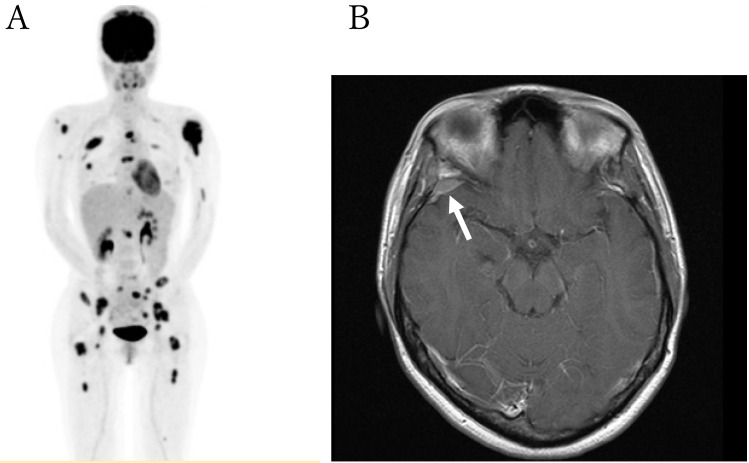

亚急性脊髓病是甲氨蝶呤(MTX)的一种罕见但严重的并发症,可导致截瘫。尽管其潜在机制尚未完全阐明,但同型半胱氨酸被认为在这一不良反应的发病机制中发挥了作用。在此,我们报告了一例 34 岁的弥漫大 B 细胞淋巴瘤女性患者,在接受改良的 CODOX-M/IVAC 方案(包括大剂量静脉注射 MTX 和鞘内(IT-)MTX)治疗后出现进行性截瘫,并伴有膀胱和排便功能障碍。在接受 S-腺苷蛋氨酸、蛋氨酸、氰钴胺和叶酸的联合治疗后,神经症状在发病后 4.5 个月内逐渐改善至基本正常水平。在化疗期间,包括治疗血液恶性肿瘤的大剂量 MTX 和 IT-MTX,应仔细评估 MTX 引起的亚急性神经元损伤,并尽早开始适当的治疗。

Subacute myelopathy is a rare but serious complication of methotrexate (MTX) that may cause paraplegia. Although its underlying mechanisms have not been fully elucidated, homocysteine is thought to play a role in the pathogenesis of this adverse effect. Herein, we report the case of a 34-years old female patient with diffuse large B-cell lymphoma who developed progressive paraplegia accompanied by dysfunctional bladder and bowel movements after treatment with a modified CODOX-M/IVAC regimen, including high-dose intravenous MTX and intrathecal (IT-) MTX. Neurological symptoms gradually improved to almost normal levels within 4.5 months of onset following treatment with a combination of S-adenosylmethionine, methionine, cyanocobalamin, and folate. During chemotherapy, including high-dose MTX and IT-MTX for hematological malignancies, MTX-induced subacute neuronal damage should be carefully evaluated, and appropriate treatment should be initiated as early as possible.